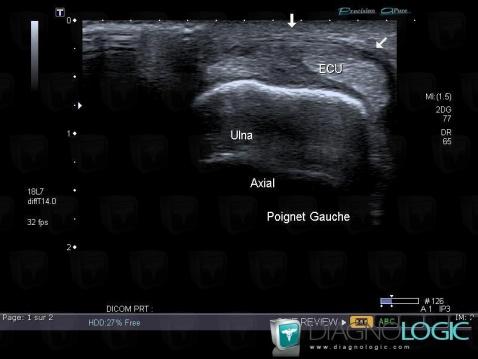

Les images ci-dessous illustrent ce dossier pour les diagnostics Luxation de l'extenseur ulnaire du carpe, pour les modalités (Echographie)

- Diagnostic Luxation de l'extenseur ulnaire du carpe, Localisation(s) Tendons/face dorsale - Poignet, comportant les gammes